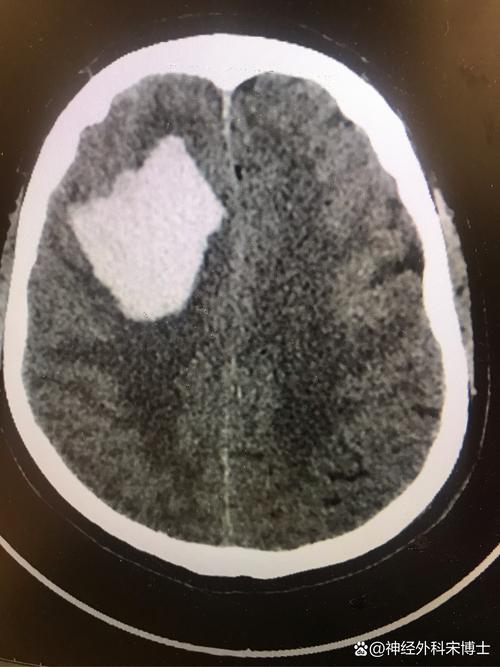

(图片来源网络,侵删)